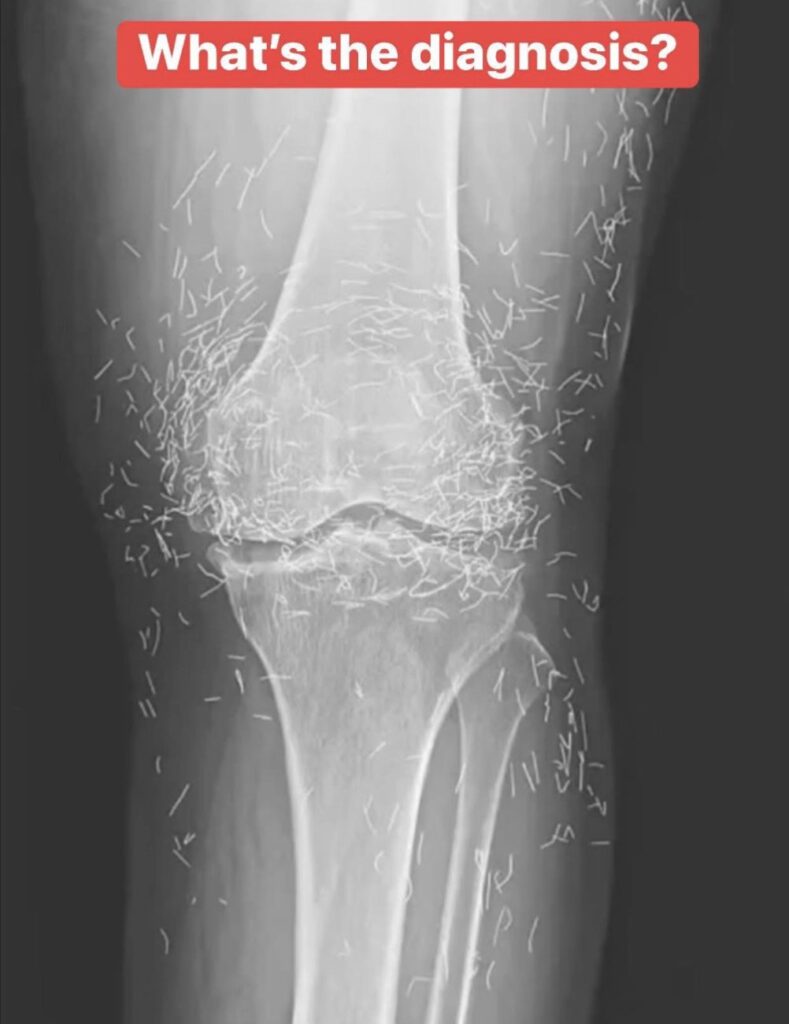

When a 65-year-old South Korean woman went in for knee pain, doctors weren’t expecting to strike gold. But that’s exactly what they found.

Acupuncture, a centuries-old alternative treatment, involves inserting needles into the body at specific points to relieve pain or treat illnesses. In this case, the needles— presumably made of gold — were intentionally left in her knees for continued stimulation.

He also warned that embedded needles can complicate X-ray readings. “The needles may obscure some of the anatomy,” Guermazi said in 2013.